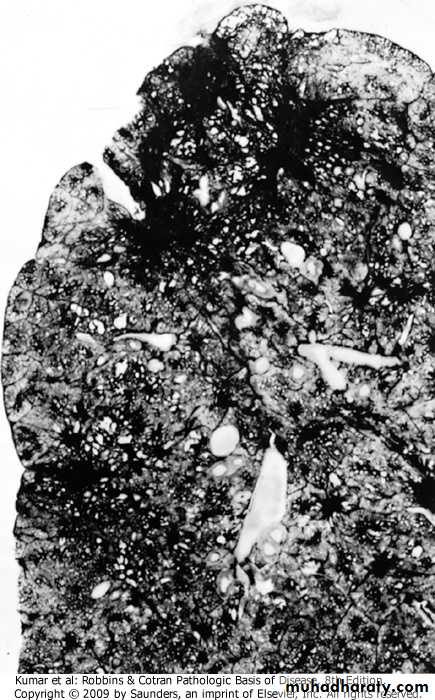

Residual strands of fibrovascular tissue in severe emphysema cross-spaces created by destruction of lung parenchymaBullous emphysema